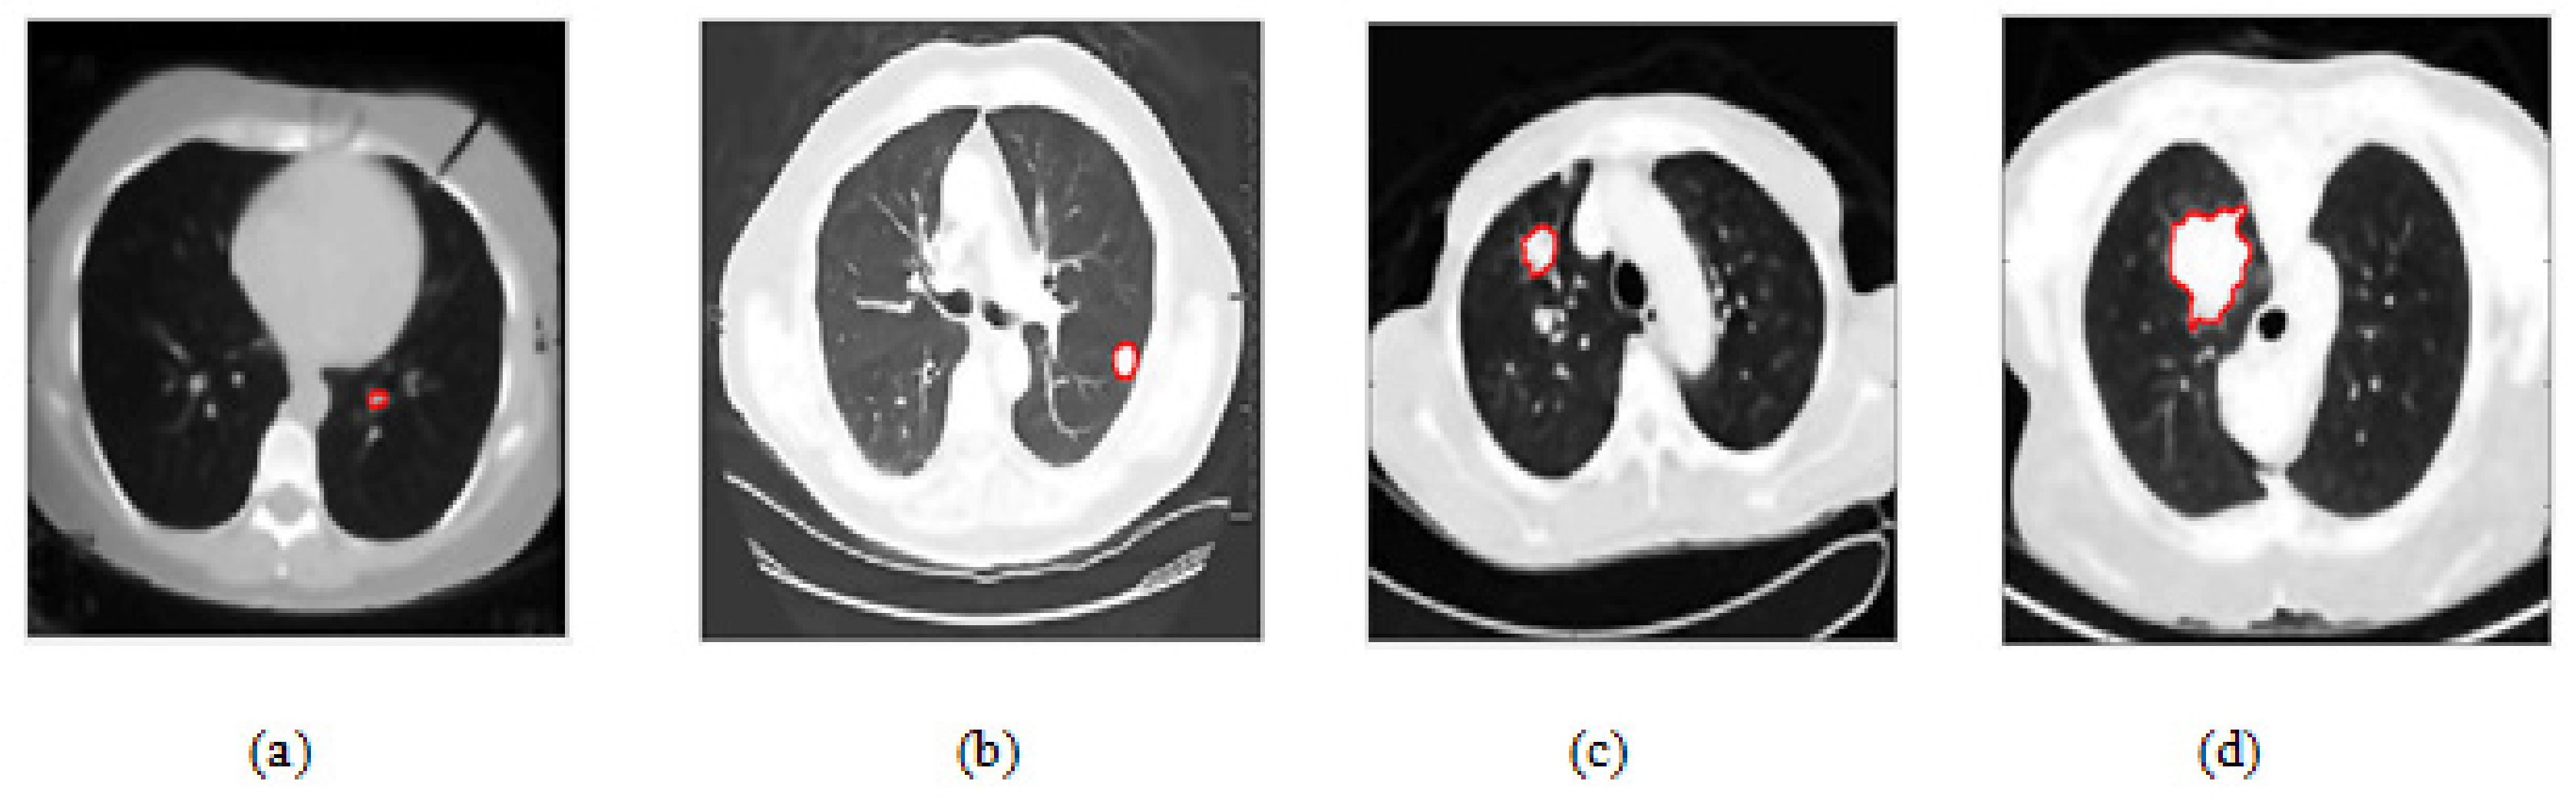

2.3. Random Walker Method for Nodule Boundary Extraction

4.2. Lung Nodule Segmentation Result